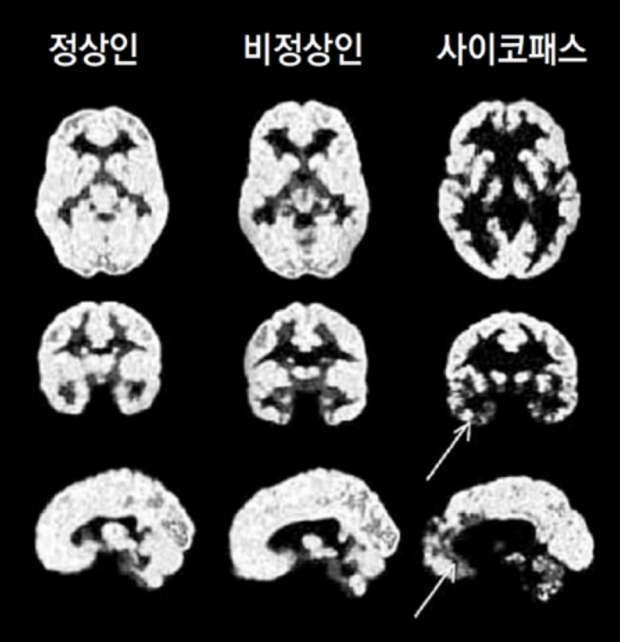

사이코패스 성향을 가진 범죄자들은 자신이 어떤 행동을 할 때, 그 행동을 하면 처벌을 받는지 안 받는지를 제대로 판단하지 못하는 것으로 나타났습니다. 세일라 호지스 몬트리온 대학 의대 교수팀은 사이코범죄자들의 재범률이 높은 이유를 맑히기 위해 사이코패스 범죄자들의 뇌를 자기 공명 영상 장치로 촬영하여 강력 범죄자, 사이코패스 범죄자, 일반일을 대상으로 각각 검사를 진행했습니다. 사이코패스 범죄자들은 사회적인 감정을 처리하는데 관여하고 있는 전문 측 전두피질과 측두극 부위가 수축돼 있는 것을 발견하였습니다. 연구팀은 사이코패스 범죄자들의 이 부분이 문제가 생기면서, 처벌을 통해 학습하지 못하는 것이라고 설명했습니다.

사이코패스와 소시오패스의 공통점은 반사회적 인격장애의 진단기준에서 찾아볼 수 있습니다. 사이코패스는 선천적으로 전두엽, 측두엽이 발달되지 않아 감정을 느끼지 못하고 공감능력이 없습니다. 소시오패스는 어린 시절의 학대 또는 사회 및 환경적 결핍요인으로 인해 성격장애가 발생된다고 합니다. 소시오패스도 사이코패스만큼은 아니지만 반사회적 행동에는 낮은 공감 능력과 부족한 양심이 깔려있다고 합니다. 소시오패스의 특징은 다음과 같습니다.